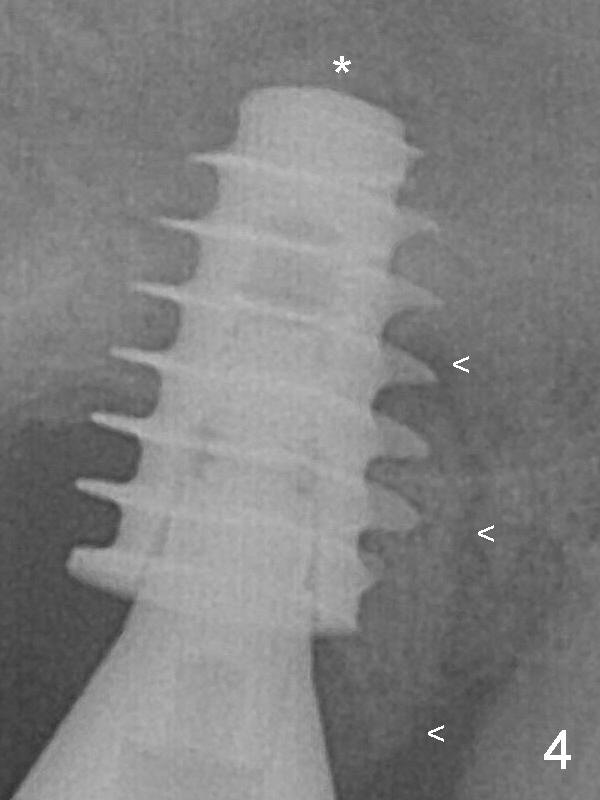

After placement of PRF membrane and bone graft (allograft, autogenous bone and Osteogen, Fig.4 *), a 6x9 mm IBS implant is placed with insertion torque of 30 Ncm. It appears that the fins of the implant slice into the bone at high magnification for engagement. Following further placement of the implant, bone graft is packed into the distal portion of the socket (<). The mesial gingiva is so thick that it is impossible to place bone graft mesial to the implant. When an implant is placed at #13 one month later, extend the incision to the mesial of #15 for bone graft. One month later, bone graft is placed mesial (Fig.8 white *) and palatal (black *) to the implant at #15 while a 3.8x13 mm implant is placed at #13 following bone expansion (using Magic Split and Magic Expander 3.0 mm). The pair abutment is changed to a healing one (6x4 mm) because of mobility 2.5 months postop. The implant seems to be stable 5.5 months postop (Fig.10), while the bone graft stays.